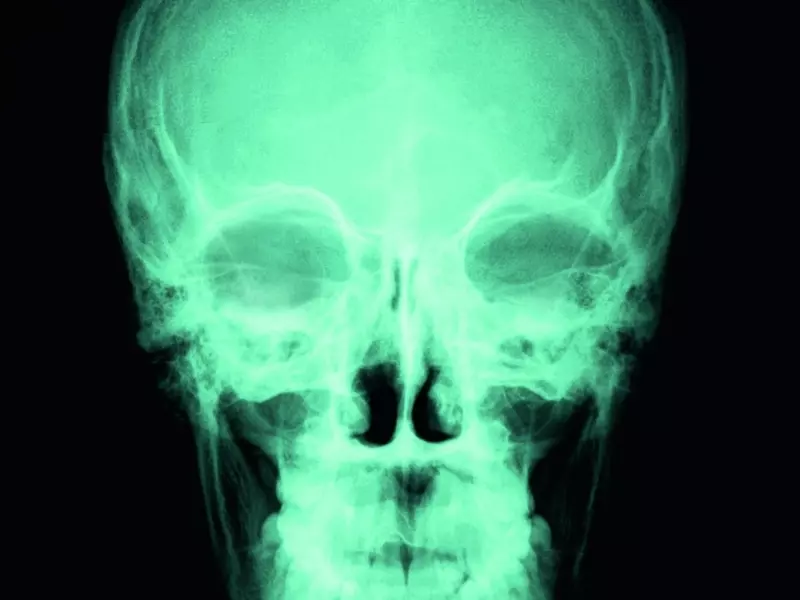

Hiperbaria tlenowa (hyperbaric oxygen – HBO) to zyskująca coraz większą popularność nieinwazyjna metoda leczenia urazów oraz chorób w komorze hiperbarycznej. Polega ona na zastąpieniu wdychanego powietrza przez 100-proc. tlen podawany pod ciśnieniem wyższym niż atmosferyczne. Na uzyskanie takich warunków pozwalają komory hiperbaryczne. W myśl aktualnych definicji o leczeniu HBO można mówić wtedy, kiedy 100-proc. tlen jest stosowany pod ciśnieniem sięgającym wartości co najmniej dwóch atmosfer absolutnych (ATA) przez przynajmniej godzinę [13]. Z uwagi na to, że tlen podawany pod ciśnieniem wyższym niż 3 ATA wykazuje działanie toksyczne, w hiperbarycznej terapii tlenowej wykorzystuje się ciśnienie rzędu 2–2,8 ATA. Zazwyczaj wynosi ono 2,5 ATA, co pozwala na wielokrotne zwiększenie ilości tlenu dostarczanego komórkom organizmu [12].